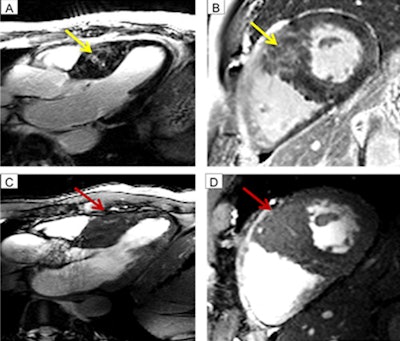

In evaluating the results, 7-tesla 2D cine FGRE image quality was rated as "good" with a mean of 1.1 (± 0.3) by one observer and 1.3 (± 0.2) by the other reader. The study also found that late gadolinium enhancement (LGE) using 7-tesla MRI was detectable in 12 (92%) of 13 hypertrophic cardiomyopathy patients.

High-spatial-resolution 7-tesla cine images also visualized minute depressions in the myocardial tissue of the left ventricle in seven subjects (54%), with all of those abnormalities located in regions positive for late gadolinium enhancement. Interestingly, 3-tesla MRI did not detect any of those deficiencies.